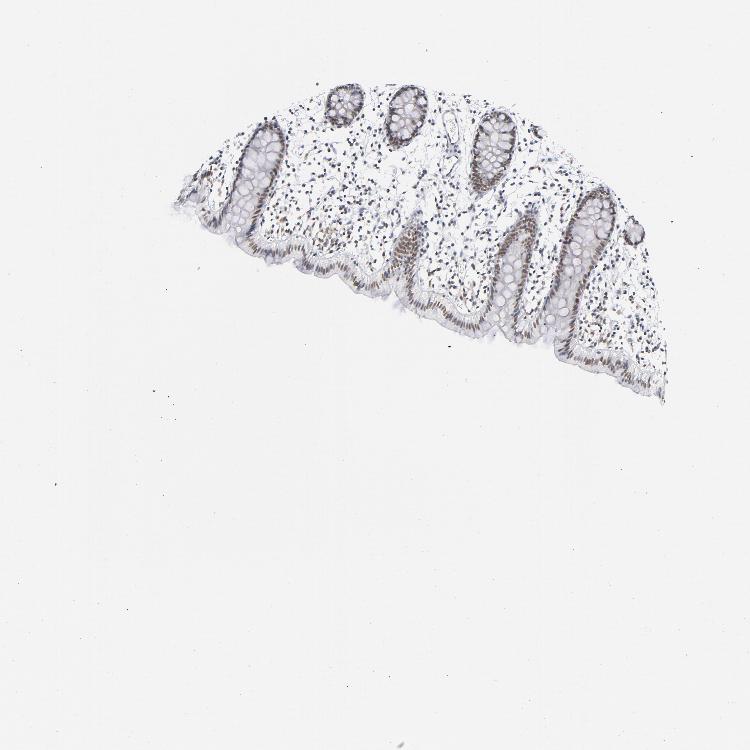

COLON - Antibody stainingi

Antibody staining in the annotated cell types in the current human tissue is reported as not detected, low, medium, or high, based on conventional immunohistochemistry profiling in selected tissues. This score is based on the combination of the staining intensity and fraction of stained cells.

Each image is clickable and will lead to virtual microscopy that enables deeper exploration of all samples and also displays staining intensity scores, fraction scores and subcellular localization as well as patient and tissue information for each sample.

Antibody HPA028814Antibody CAB004322

Endothelial cells MediumNot detected

Glandular cells MediumMedium

Peripheral nerve/ganglion LowNot detected